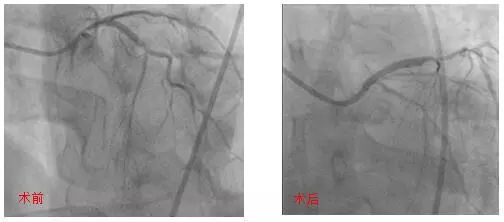

技艺精湛处理无保护左主干病变

来自黑龙江的李先生患有糖尿病、高血压多年,6年前因为冠心病、三支血管堵塞做了冠脉搭桥手术,但手术后未能按时服药,最近半年来再次出现活动后胸痛。外院复查冠脉CT,发现搭桥的血管闭塞,自身的血管状况较差,左主干狭窄70%,前降支及回旋支狭窄80-90%,右冠状动脉闭塞。

左主干严重狭窄,桥血管及右冠全部闭塞,这是最危险的无保护左主干病变,冠脉介入治疗是目前唯一的希望。

李先生通过朋友打听到北京大学国际医院,满怀希望地来到了心血管内科就诊。经过完善的术前准备后,银鹏飞主任医师、张文超副主任医师一起为李先生进行了手术,但手术过程比预想的更艰难,右冠状动脉闭塞时间太长,经过反复尝试仍然不能开通。为了开通维持生命的血管,银鹏飞主任医师选择了风险更高的策略:直接处理左主干病变。

通过精确定位,采用Crossover技术在左主干-前降支植入1枚支架,回旋支应用新技术-药物球囊扩张处理。手术后李先生症状明显缓解。